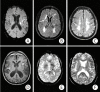

Cerebral small vessel disease (cSVD) has a crucial role in lacunar stroke and brain hemorrhages and is a leading cause of cognitive decline and functional loss in elderly patients. Based on underlying pathophysiology, cSVD can be subdivided into amyloidal and non-amyloidal subtypes. Genetic factors of cSVD play a pivotal role in terms of unraveling molecular mechanism. An important pathophysiological mechanism of cSVD is blood-brain barrier leakage and endothelium dysfunction which gives a clue in identification of the disease through circulating biological markers. Detection of cSVD is routinely carried out by key neuroimaging markers including white matter hyperintensities, lacunes, small subcortical infarcts, perivascular spaces, cerebral microbleeds, and brain atrophy. Application of neural networking, machine learning and deep learning in image processing have increased significantly for correct severity of cSVD. A linkage between cSVD and other neurological disorder, such as Alzheimer's and Parkinson's disease and non-cerebral disease, has also been investigated recently. This review draws a broad picture of cSVD, aiming to inculcate new insights into its pathogenesis and biomarkers. It also focuses on the role of deep machine strategies and other dimensions of cSVD by linking it with several cerebral and non-cerebral diseases as well as recent advances in the field to achieve sensitive detection, effective prevention and disease management.